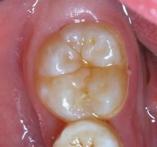

牙齿的窝沟封闭, 主要是为了防止窝沟龋的发生。 一些新萌出的恒牙,主要是六龄齿,它的咬合面会因为发育过程中形成的比较深的窝沟。在萌出之后,细菌、食物残渣就容易堆积在这个位置,而成为龋病容易发生的部位。

去年12月,7岁的佳佳在家长的陪同下来到两江二院口腔科做检查。家长告诉李仁文医生,佳佳 比较喜欢吃零食 ,很担心她有蛀牙。 李医生检查后,发现佳佳的口腔状况尚好,但磨牙合面窝沟深,建议她做个窝沟封闭。与她俩沟通后,李医生为佳佳行窝沟封闭术,先清洁牙面、酸蚀,再涂布窝沟封闭剂。